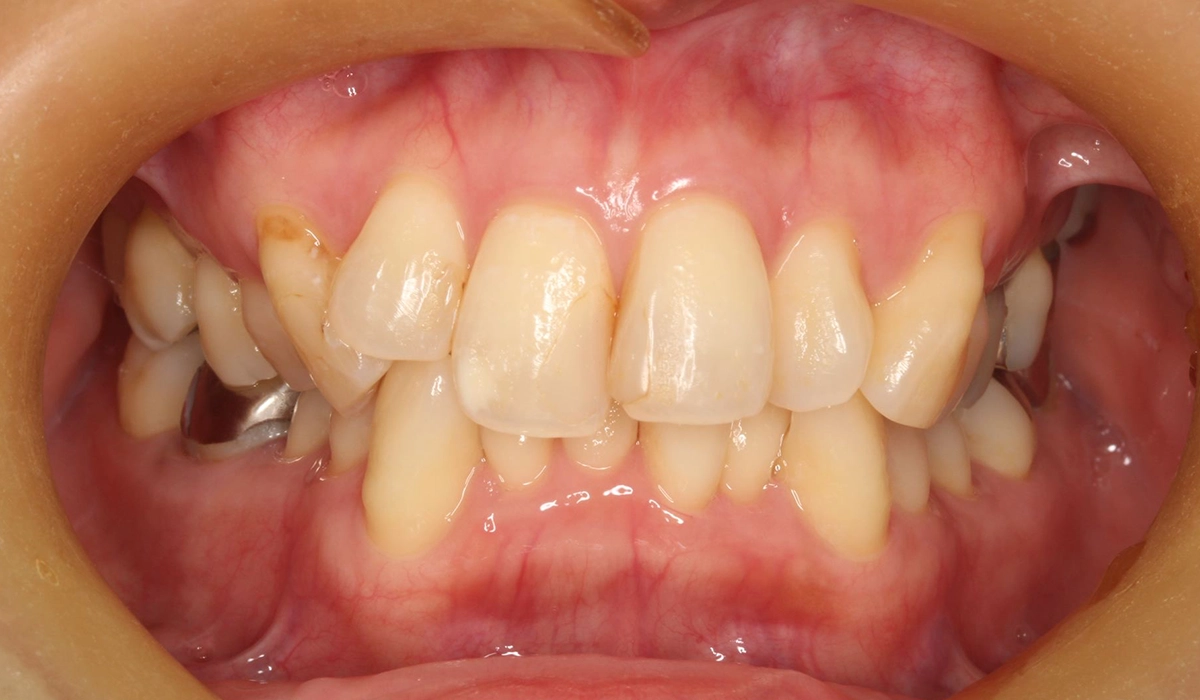

今回ご紹介する患者様は、全体的な歯のがたつきを気にされており、矯正検査後Ⅰ級叢生と診断。抜歯適応症例だが患者様希望により歯肉退縮を許容したうえで非抜歯で仕上げている。

術前:正面

| 主訴 | 全体的な歯のがたつきを気になる |

| 治療期間 | 24カ月 |

| 治療費用 | 990,000円(税込) |

| 治療内容 | 患者様は全体的な歯のがたつきを気にされており、矯正検査後Ⅰ級叢生と診断。抜歯適応症例だが患者希望により歯肉退縮を許容したうえで非抜歯で仕上げている。 |